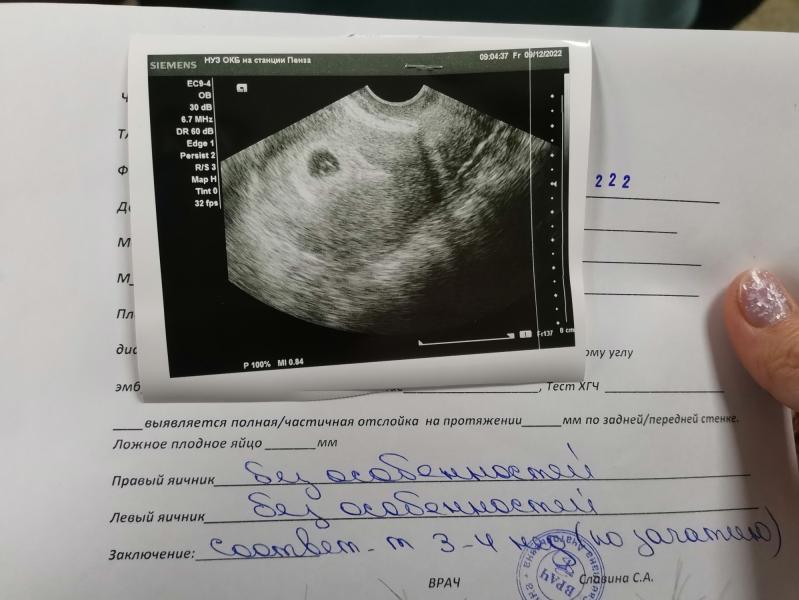

Наша первая фотография 😁

Так боялась идти на узи, начиталась тут всевозможных случаев и накрутила себя

Но благо на данном этапе все хорошо

Судя по размерам эмбриона, ПЯ тогда где то около 15мм)

Сколько мм плодное яйцо?